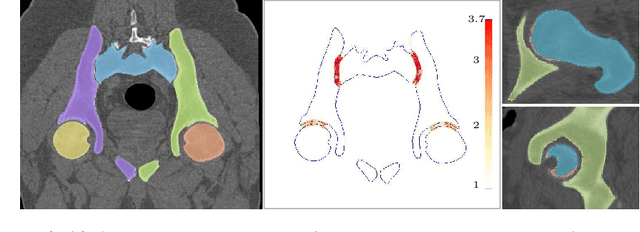

Abstract:We present a method to generate subject-specific cartilage for the hip joint. Given bone geometry, our approach is agnostic to image modality, creates conforming interfaces, and is well suited for finite element analysis. We demonstrate our method on ten hip joints showing anatomical shape consistency and well-behaved stress patterns. Our method is fast and may assist in large-scale biomechanical population studies of the hip joint when manual segmentation or training data is not feasible.